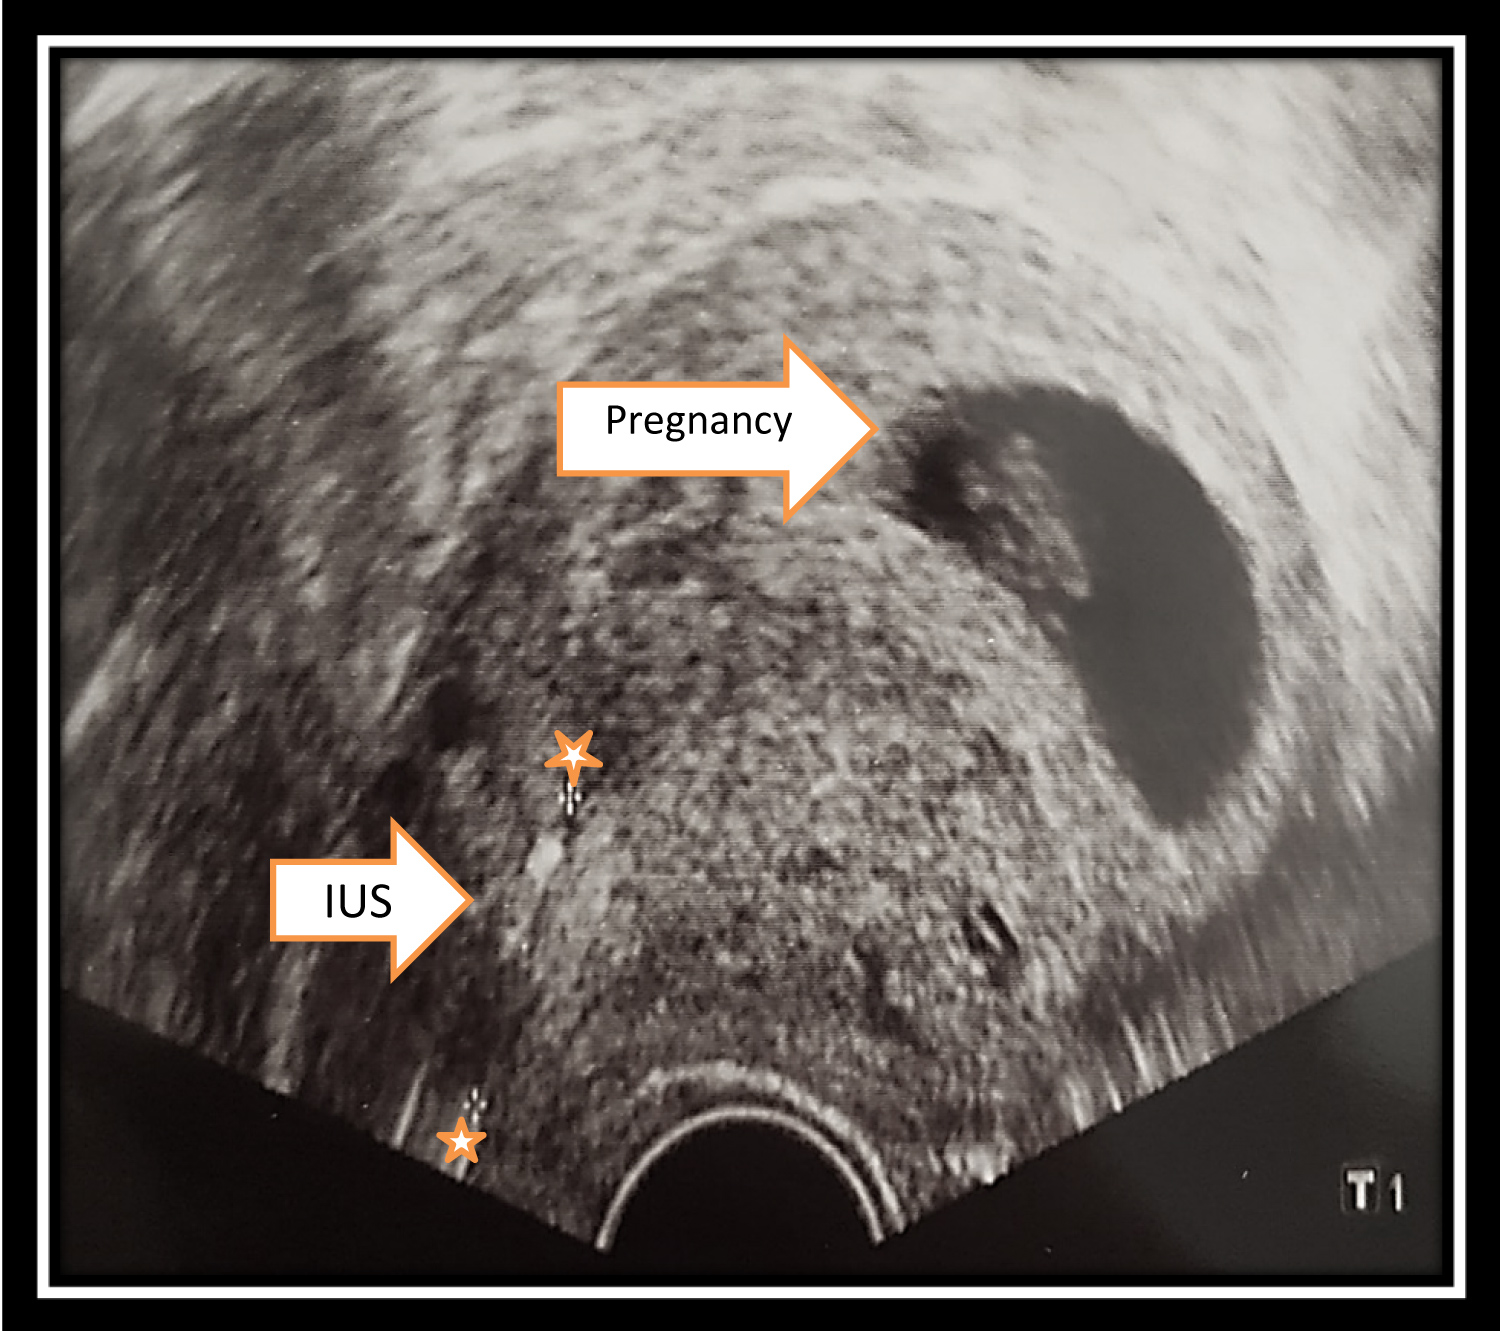

We present the case of a 28-year-old GII/PI woman who was admitted to us due to pregnancy with LNG-IUS 52 mg in the 9th gestational weeks. Sonography showed an intact pregnancy corresponding to the gestational week. The IUS was located in the lower part of the cavity at a considerable distance from the amniotic cavity (Figure 1 and Figure 2).

Figure 1: Removal of the IUS under hysteroscopic control. View Figure 1

Figure 2: Pregnancy with IUS. View Figure 2